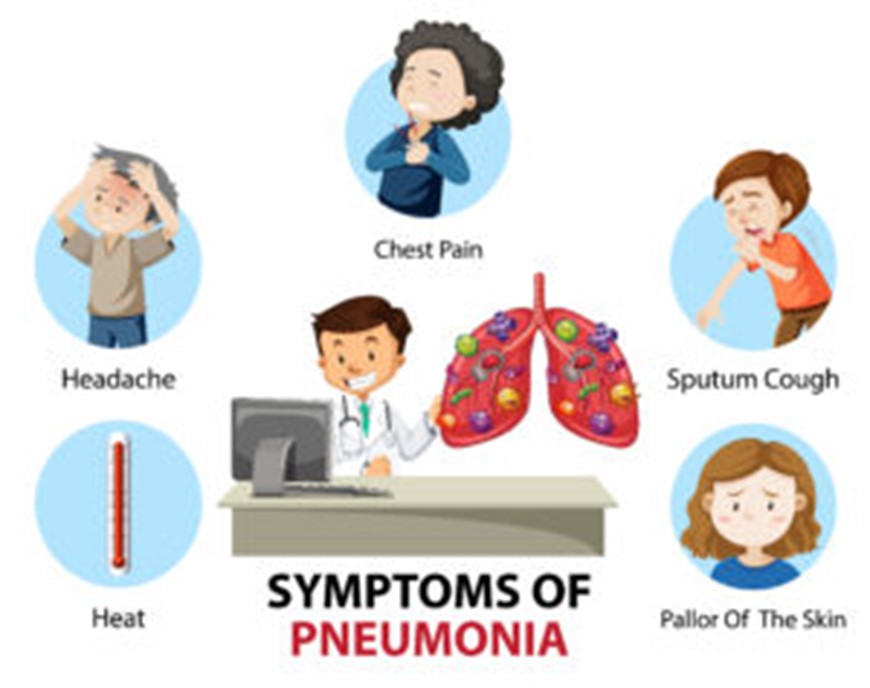

A diagnosis of bacterial pneumonia is based primarily on chest x-ray findings, white blood cell count, and a sputum culture together with fever, recurrent chills, cough, shortness of breath (i.e., dyspnea), and abnormal chest sounds (6).

Physical examination findings vary depending on the type of microorganism, severity of pneumonia, age of the patient, coexisting host factors, and presence of complications and

may include the following: fever or hypothermia, shallow breathing, tachycardia or bradycardia, cyanosis, decreased breath sounds, crackles (rales) with auscultation of the lungs, egophony on auscultation, pleural friction rub, dullness of the chest to percussion, altered mental status (especially confusion) (7).